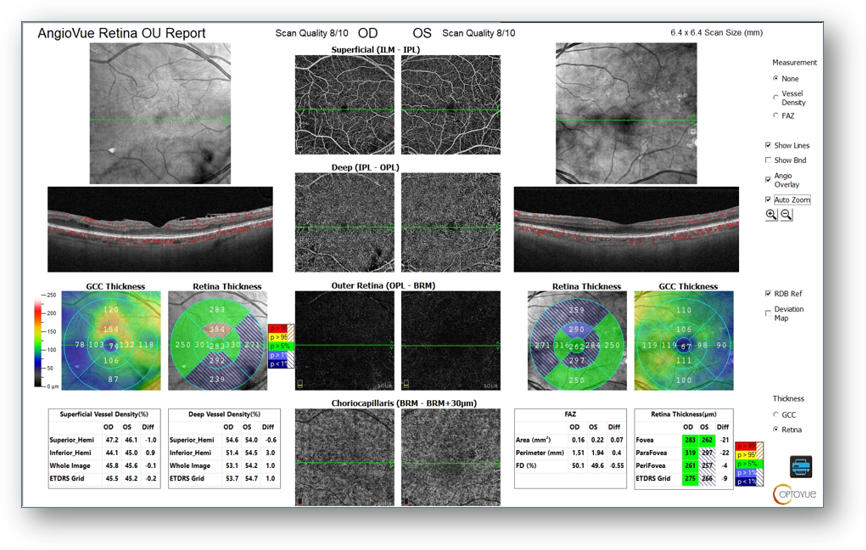

There was also evidence of ongoing vascular changes on OCT-A, including an irregular/asymmetric foveal avascular zone and capillary dropout (Figure 2) along with moderate ERM OD with central microaneurysms on OCT (Figure 3). As such, I wanted to monitor for progression that might require additional intervention.

Figure 2: OCT-A

Figure 3: OCT